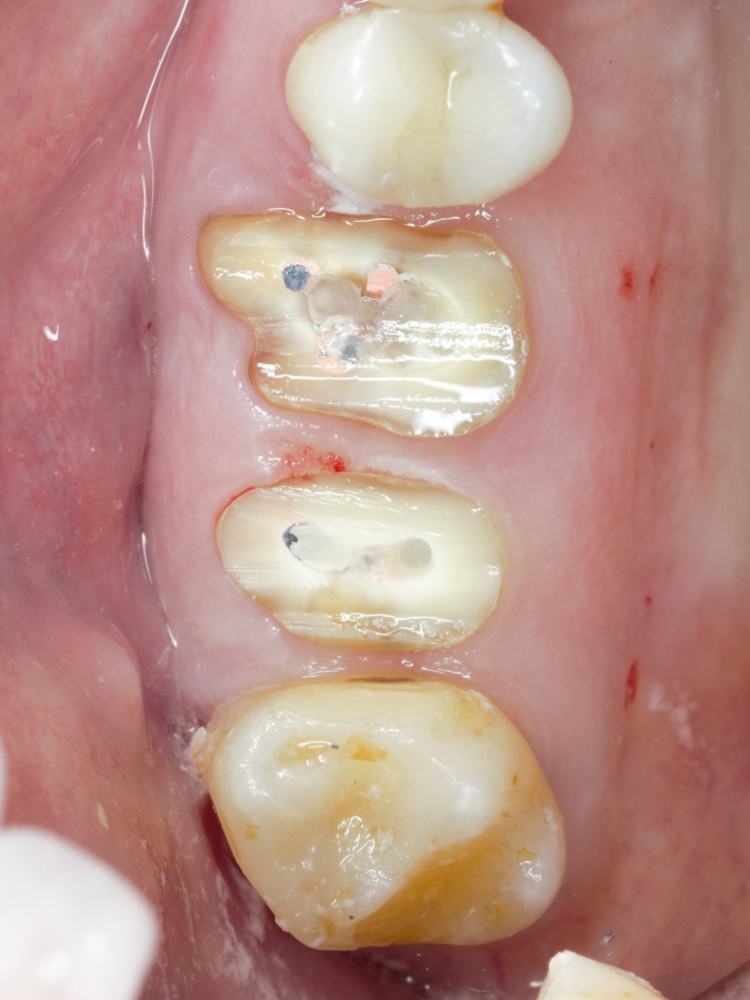

Вот клиническая картина через 4 месяца после ранее проведенной имплантации с остеопластикой:

Как видишь, коллеги из недалекой дружественной страны не осилили снятие швов. Мне это не нравится, хотя и объясняет, почему люди готовы ехать за тыщи километров ради 20-минутной операции удаления зуба мудрости.

Ну хорошо. Швы сняли. Делаем разрез. Обрати внимание, что после всех проведенных операций у нас остается очень небольшой по ширине слой жевательной слизистой оболочки:

Через неделю я снял швы, а мой коллега Андрей Карнеев (дело было еще в НИЦ) приступил к изготовлению протезов. На это ушло полторы недели:

Ремарка: Во всех случаях "сложной" имплантации первым делом изготавливаются временные коронки на срок до 12 месяцев. Здесь мы провели остеопластику одновременно с имплантацией - и это вполне катит за "сложную" имплантацию и требует изготовления временных коронок на минимальный срок 6 месяцев.

«Ого, какие классные зубы!» — сказала тогда Зинаида, после чего мы попрощались и договорились встретиться через полгода-год для замены временного протеза на постоянный керамический. Зинаида вернулась домой, в дружественную среднеазиатскую страну.